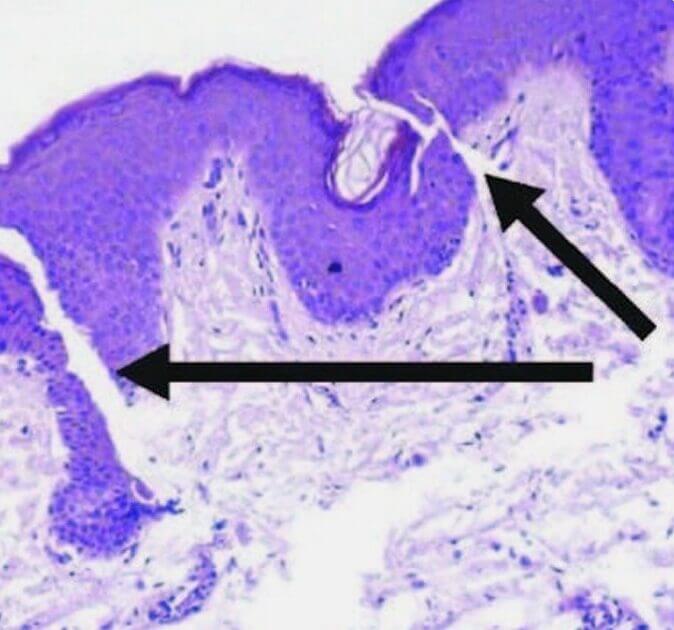

Stretch Marks

Stretch Marks

Normal Skin

Smooth and elastic with intact collagen and elastin fibers maintaining firmness and structure.

Striae Rubrae

Smooth and elastic with intact collagen and elastin fibers maintaining firmness and structure.

Striae Albae

Mature white stretch marks where collagen remodeling leads to thinning and loss of pigmentation.

How it works

- Promotes removal of damaged collagen

- Induces keratinocytes proliferation that releases growth factors to promote collagen deposition by the fibroblasts and elastin deposition

- Modulates the expression of several genes in the skin (vascular endothelial growth factor, fibroblast growth factor, epidermal growth factor, collagen type I and III) that promote extracellular matrix remodeling